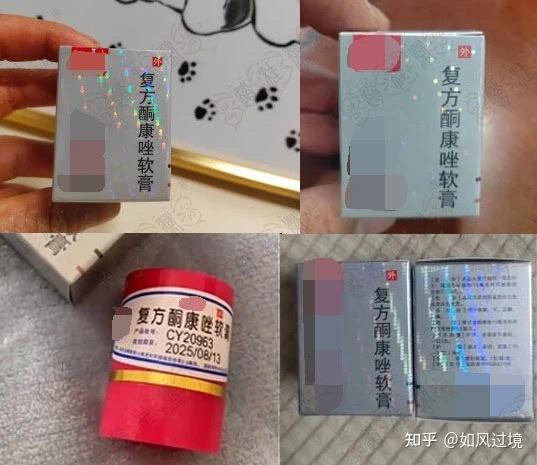

皮康王(复方酮康唑乳膏)有很大副作用吗?

皮康王酮康唑乳膏的主要功效如下1 广谱抗真菌作用皮康王的核心成分酮康唑属于咪唑类抗真菌药物,通过抑制真菌细胞膜中麦角固醇的合成,破坏细胞膜完整性,从而发挥杀菌或抑菌作用其对皮肤癣菌如红色毛癣菌须癣毛癣菌酵母菌如白色念...